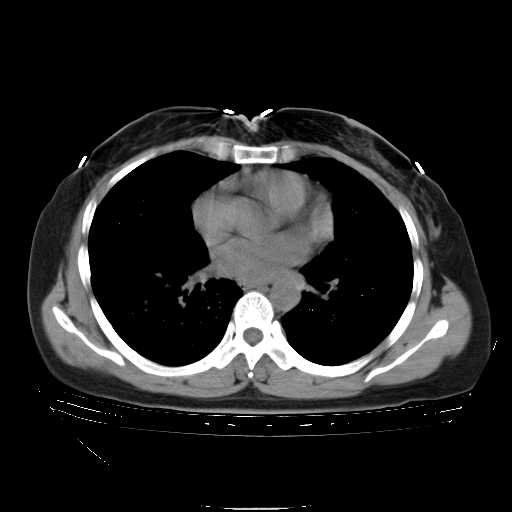

f50,肺ca治疗后,做过穿刺,确诊是肺ca,大家看看这是去年12月做的